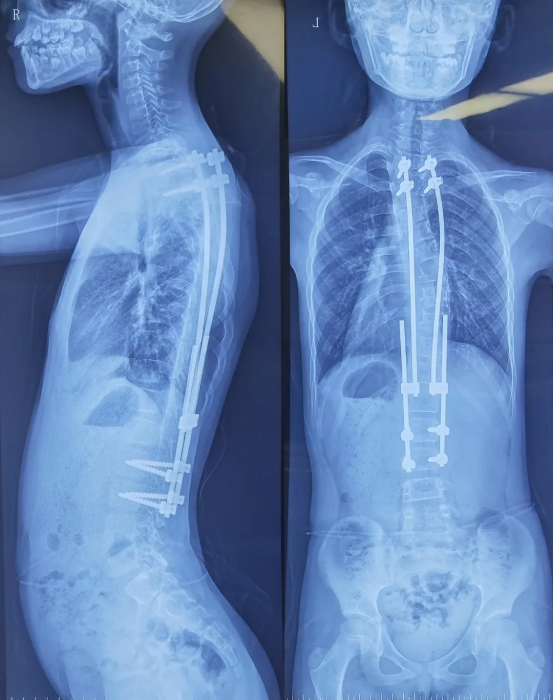

Age: 10 years

Gender: Female

Procedure: Spinal revision surgery

The patient initially underwent fixation with growing rods. However, due to rapid growth, the original fixation system could no longer accommodate her growth. A revision surgery was therefore required to adjust the fixation device and re-correct the spinal deformity.

Preoperative imaging of the pediatric patient

Pediatric spinal revision surgery is far more complex than primary surgery. The core challenges lie in anatomical adhesions and limited surgical visibility. The initial operation oftentends to induce scar tissue formation around the spinal column, which adheres muscles, blood vessels, and nerves to adhere to the spine and internal fixation devices, significantly increasing surgical difficulty. At the same time, scar-induced visual obstruction blurs the surgical field and impairs the surgeon’s ability to accurately identify spinal segments.